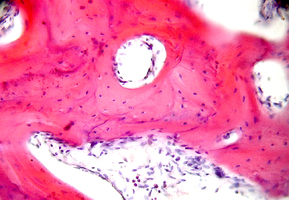

2. Поверхность и структура материала для изготовления биоимплантатов

4. Схема деминерализации материала для получения ДМ-форм

6. Полное замещение биоимплантатов собственными тканями организма